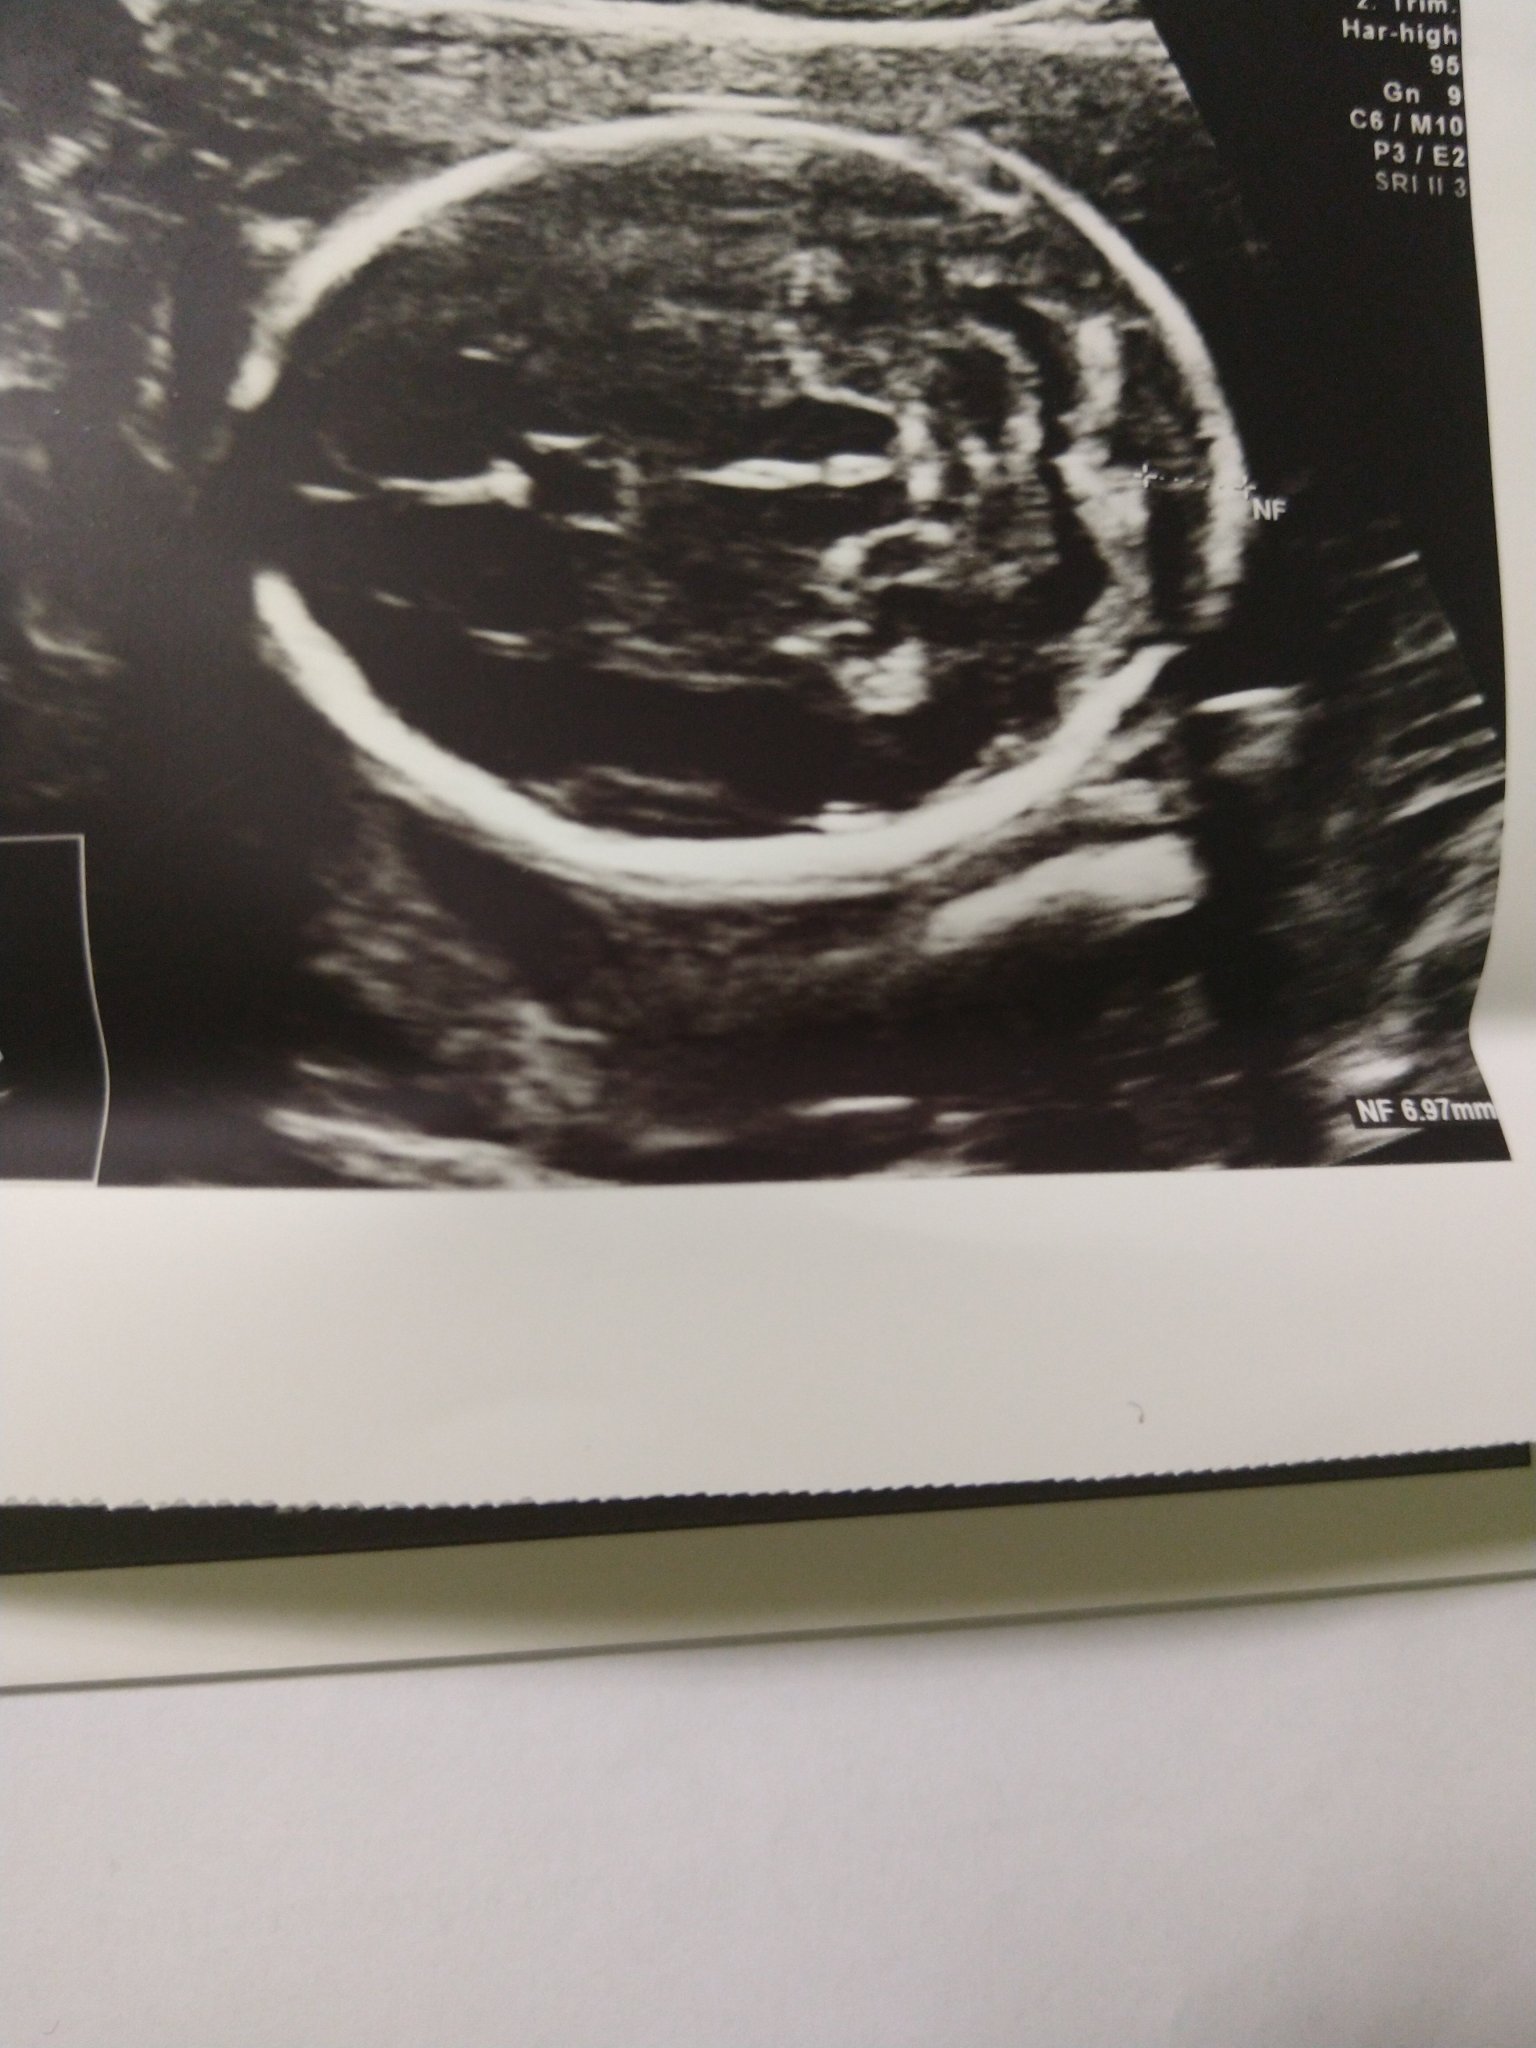

За 20гс до 6мм. При БХС в 13.г.с си беше в норма, сега на едната ФМ я измериха 6.98мм обаче отгоре някак си гледано ще прикача снимка. Иначе като направих още една контролна ФМ повече от 4мм(странично гледане на бебето) не можа да я измери.